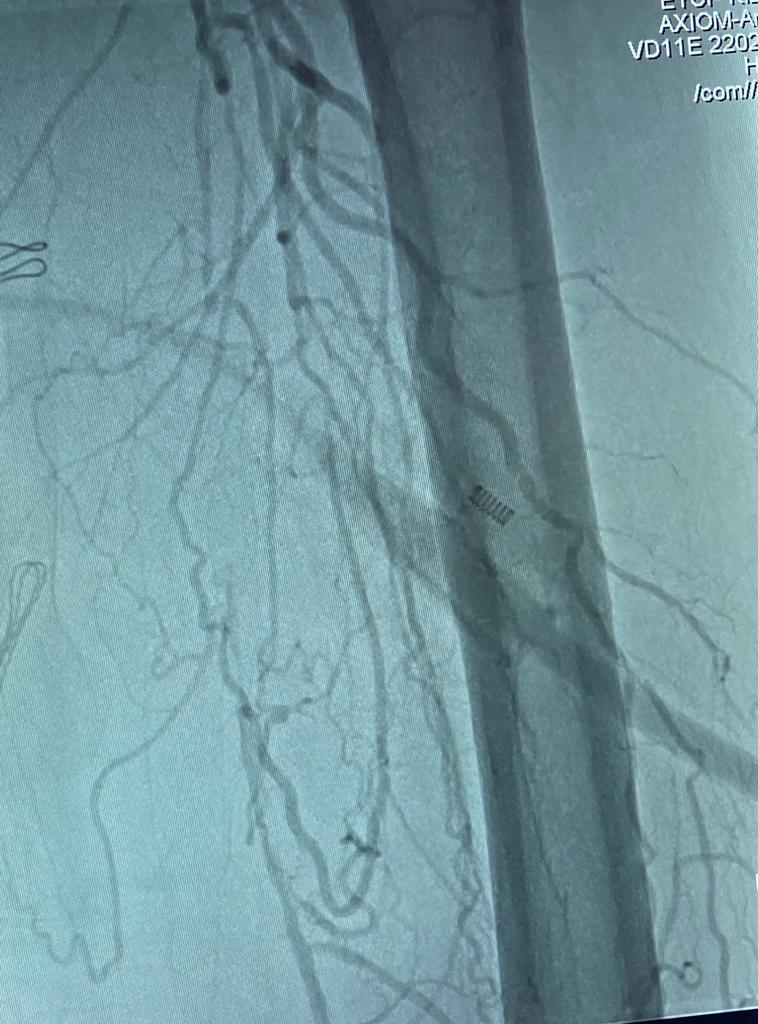

Hastanın daha önce böbrek taşı nedeniyle sol böbreğinin ameliyatla alındığını ayrıca damar hastalıkları nedeniyle karındaki aort damarından her iki kasığa uzanacak şekilde sentetik damar kullanılarak baypas ameliyatı olduğunu ifade en Yetüt, yapılan tetkikler sonucunda her iki kasıktan bacağa giden damarlarda tıkanıklık olduğunu tespit ettiklerini belirtti. Hastanın mevcut riskli hastalıkları ve damar yapısını değerlendirerek hastaya HİBRİT ameliyat planladıklarını söyleyen Yetüt, şöyle ifade etti

“Hastamızın, sağ bacağındaki damar tıkanıklığının anjiyoya uygun olmadığını ve ameliyatla açılabileceğini ve diğer bacağın anjiyo için uygun olduğunu değerlendirip karar verdik. Daha hızlı ve daha az komplikasyon için her iki bacağa aynı seansta hastayı uyutmadan belden uyuşturarak, hasta ile iletişim halinde önce ameliyata alınıp sağ bacağına sentetik damar ile baypas yaptıktan sonra hasta, ameliyathane ile bitişik olan anjiyo birimine alındı. Hastanın diğer bacağına kesi yapmadan böbrek için zararlı olan kontrast ilacını daha az vererek kapalı olan diğer bacağındaki damarı anjiyo ile açtık. İşlem sonrası hasta yoğunbakım ihtiyacı olmadan kalp ve damar cerrahisi servisine alındı. 2 gün serviste takip edildikten sonra herhangi bir komplikasyon yaşanmadan hastanın şikayetleri tamamen geçerek hasta şifa ile taburcu edildi.”